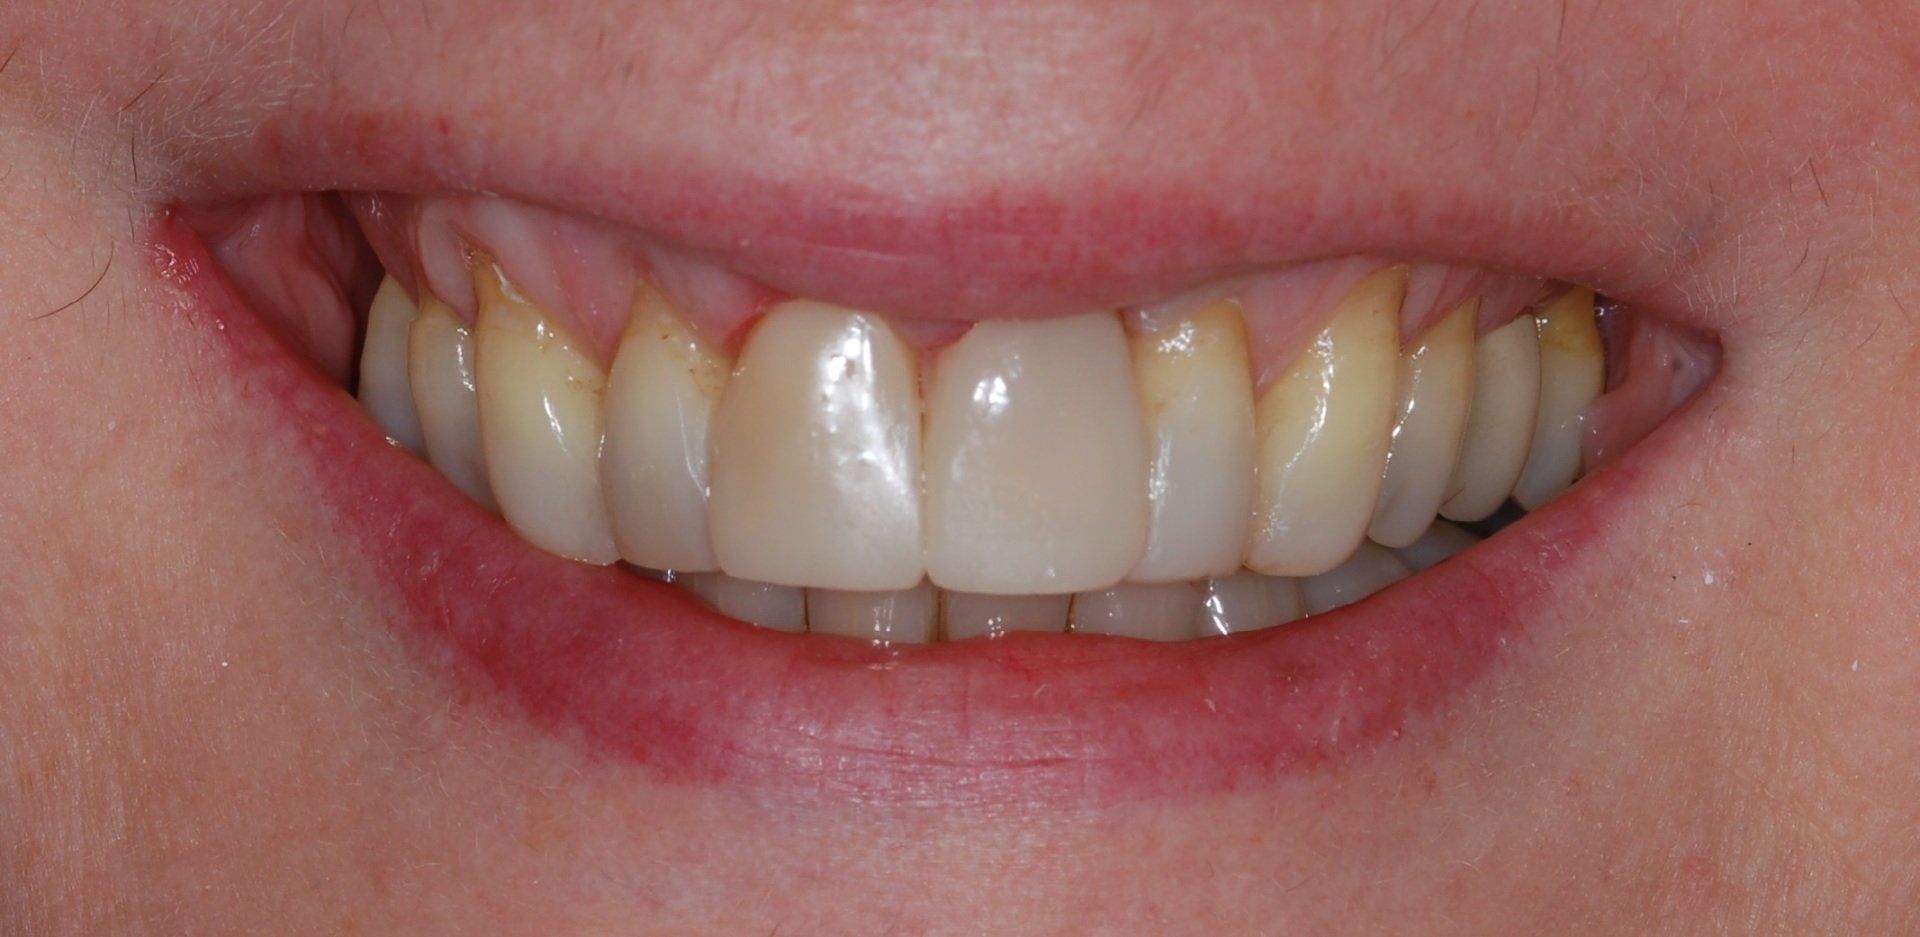

Porcelain Crowns

This patient was unhappy with the short length and discolouration of her teeth. We did a wax up study to evaluate the ideal size and length for her teeth. We then proceeded with six anterior porcelain crowns.